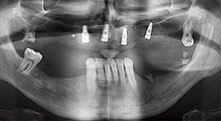

Professor Dr. Dr. Emanuel Bratu, maxillofacial surgeon, oral surgeon and prostheticist, is head of the implantology departments at two Romanian universities. He runs a renowned private hospital in Timisoara and is an internationally known researcher. In the interview Bratu explains why he considers that the W&H Piezomed piezosurgical device, and particularly two patented saws, have become essential for bone surgery.

Bratu: We routinely use the instruments for harvesting bone blocks and splitting alveolar ridges. We also use the Piezomed B6/B7 for osteotomy of impacted teeth and removing failed implants. All indications that require deep, clean cuts.

Bratu: We prefer to harvest bone from the external oblique ridge of the posterior mandible, not from the interforaminal region. After the soft-tissue incision, we use the new saws to define the amount of bone to harvest. With this approach, we also use them for the entire preparation in almost 80% of cases. We may also use other piezo instruments and then at the end a chisel to mobilize the block. We find that this is a very effective surgical technique.

Bratu: We like to use the sandwich technique for augmentation in the lateral mandible. A bone cover is prepared with the piezo saw and the crestal fragment is fixed with microscrews. We place a mixture of autologous bone and xenogenic bone replacement material in between. This works very reliably. You should always ensure sufficiently dimensioned vertical cuts when splitting the alveolar ridge in the mandible. Otherwise the bone may fracture easily.